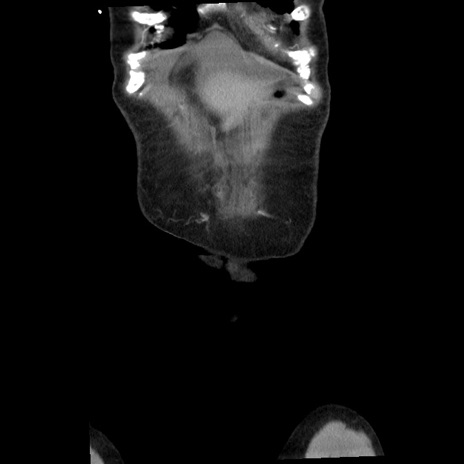

矢状断像